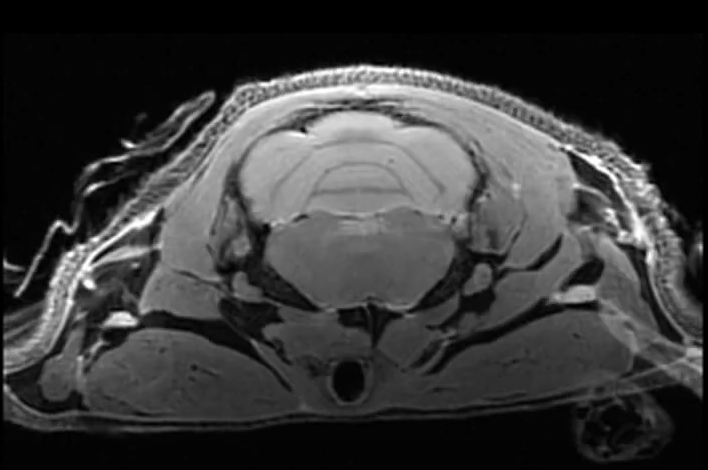

Examples of images acquired by our 7T MRI

MRI images of rat spine, brain tumor, fat imaging and mouse in-utero